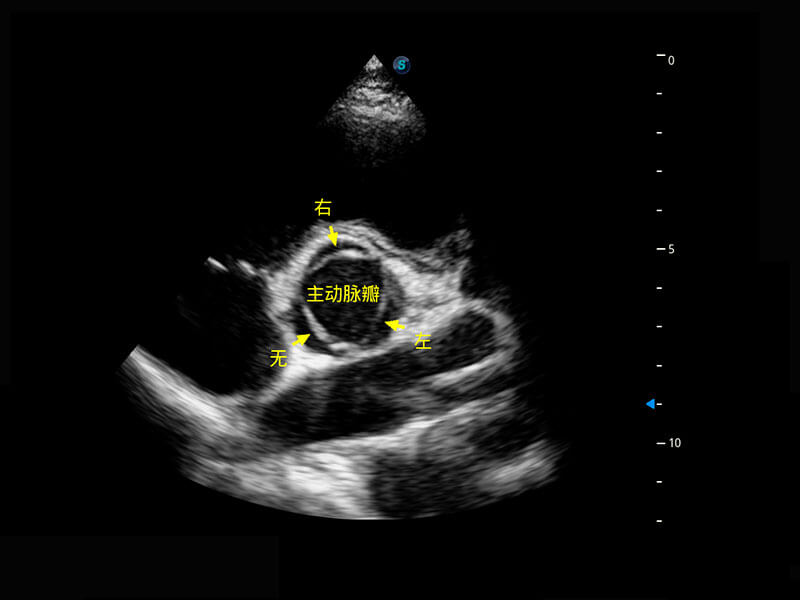

P60搭载一系列胎儿心脏成像技术,实现精细的胎儿心脏评估。

四腔切面

四腔心血流